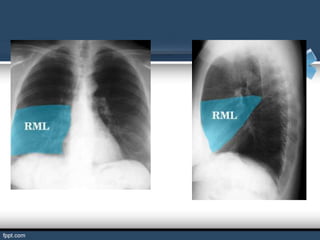

BRONQUIOS LOBARES

El bronquio principal derecho se divide en los llamados bronquios

lobares (son tres: superior, medio e inferior). El bronquio principal

izquierdo se divide a su vez en bronquios lobares (son dos: superior

e inferior).

Los bronquios lobares derecho e izquierdo se subdividen a su vez en

bronquios segmentarios o terciarios por cada lado.